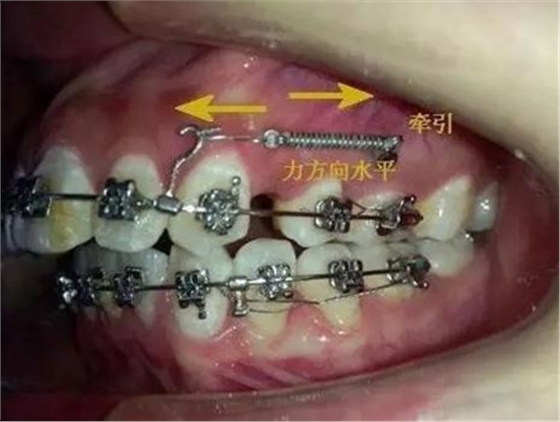

考慮到如果能像種植支抗,水平方向或者向唇側(cè)牽引移動,可以有效避免垂直方向牽引力壓迫側(cè)切牙根尖部,所以我和病人溝通了一下,建議采用種植支抗,但是病人不想增加費用。

那好吧還是采用輔弓增加支抗,經(jīng)濟適用,也便與操作,0.8不銹鋼絲彎制,進行熱處理,增加其彈力。

結(jié)扎固定